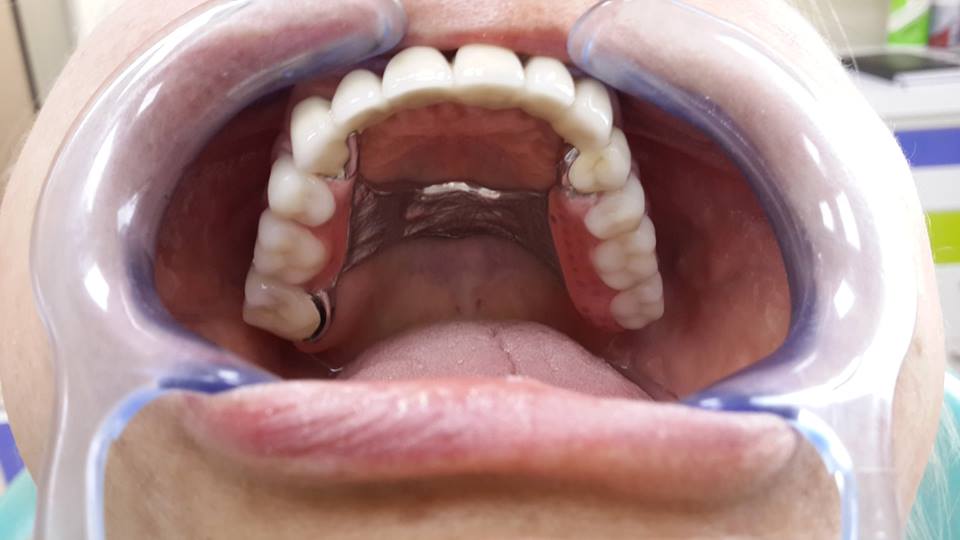

An example of complete rehabilitation of the oral cavity. Treatment included the removal of the old prosthesis, treatment of paradontitis, removal of a large cyst, implantation, clasp prosthesis.